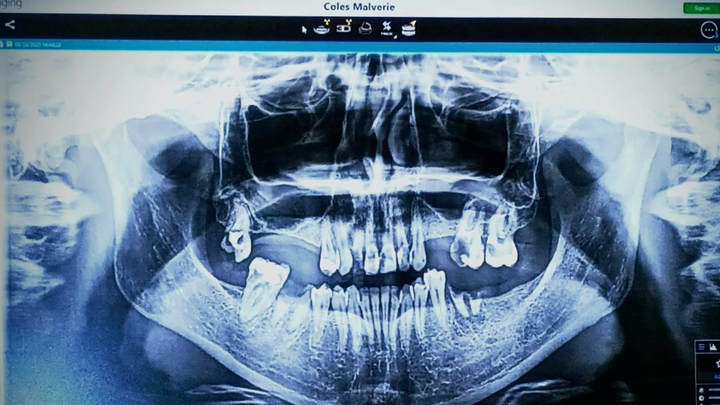

My name is Malverie, and I am reaching out to my community for support as I face a significant medical challenge. I am in need of permanent dentures or dental implants, which are essential not only for my personal confidence and oral comfort but also for protecting my oral health and potentially my overall well-being. This journey has been difficult, and the costs associated with these procedures are more than I can manage on my own.